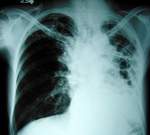

Мой муж не прошел годовой мед.осмотр (машинист метро). Подозрение на туберкулез. В городском диспансере ничего сказать не могут ( Какая-то зараза есть. а вроде и нет)

В областном диспансере (г. Москва, пл. Борьбы) тоже ничего не говорят. Только сказали, что нужно делать биопсию-а это разрезать, брать кусок "материала" и т.д. Можно ли как-то провести обследование "бескровно". Пусть за деньги. Все что нужно.